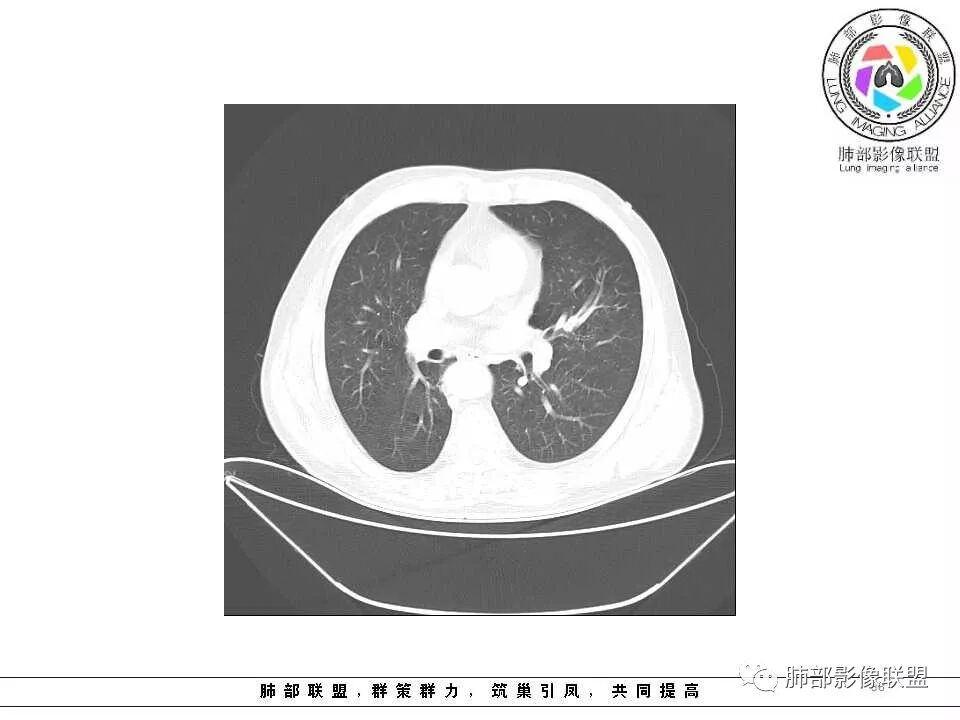

影像学特点:肺气肿背景下在大概一年的时间里出现了一个光滑的小结节,因为图像给的不是太薄,与支气管的关系判断不清,从结节周围出现斑片状炎症来判断,应该考虑结节位于支气管内,周围是阻塞性炎症,这样比较容易解释咯血

老年男性,左肺舌段见多个小结节灶及斑片状高密度灶、磨玻璃影,结节灶边界清晰,光滑,无明显分叶,密度均匀,周围病灶密度不均,一年内生长,考虑恶性肿瘤并阻塞性肺炎出血,小细胞可能大。

老年男性,肺气肿基础。约一年时间出现左肺上叶舌段支气管近端结节影,远端斑片样阴影,边缘模糊。考虑近端恶性占位,远端有阻塞性炎症。

肺气肿背景,2016年左肺上叶上舌段见微结节,2017年5月左肺结节增大,密度均匀,边缘光滑锐利,与邻近血管关系密切,血管贴壁走行,外侧见尖状突起,下舌段片状影,沿着支气管走行,内有粘液栓,考虑鳞癌,鉴别小细胞肺癌。

肺气肿背景,2016年左肺上叶上舌段见微结节,一年后左肺结节增大,密度均匀,边缘光滑、膨隆,似见小分叶,下舌段片状影,沿着支气管走行,内,老年患者,咯血1月。考虑恶性病变并阻塞性肺炎,鳞癌?注意鉴别结核。

老年男性,咯血1月,肺气肿背景,16年左肺上叶舌段结节,左肺门疑似淋巴结肿大,呈结节感。17年左肺上叶舌段见沿支气管走行分布结节 远端阻塞性肺炎,左肺门淋巴结肿大明显,首先考虑恶性病变,鳞癌?类癌?